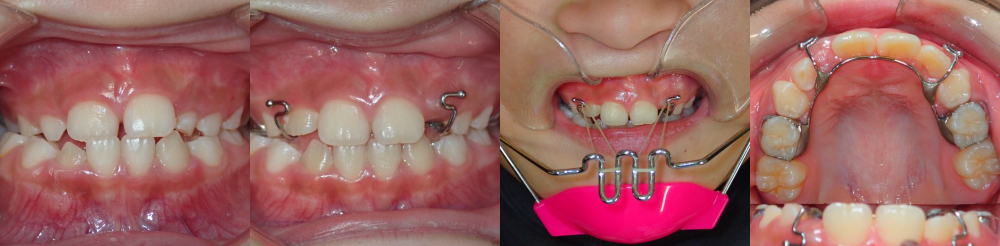

■シールド状マウスピースの間違った使い方で生じた開咬状態

■シールド状マウスピースの間違った使い方で生じた開咬状態

インビザラインは歯の傾きや位置が原因で受け口が生じている場合に効果的ですが、残念ながらこちらにも骨格的な問題の解決は期待できません。そのため当院では、まず顎外装置(お口の外で使用する装置)を使って上下の顎関係の改善を優先し、その後の仕上げで前歯を綺麗に並べるためにインビザラインを用いることが多いです。顎外装置を使わないと、上顎の成長促進は行えません。

写真左から/初診、改善直後,装着時の様子、お口の中の装置

写真左から/初診、改善直後,装着時の様子、お口の中の装置